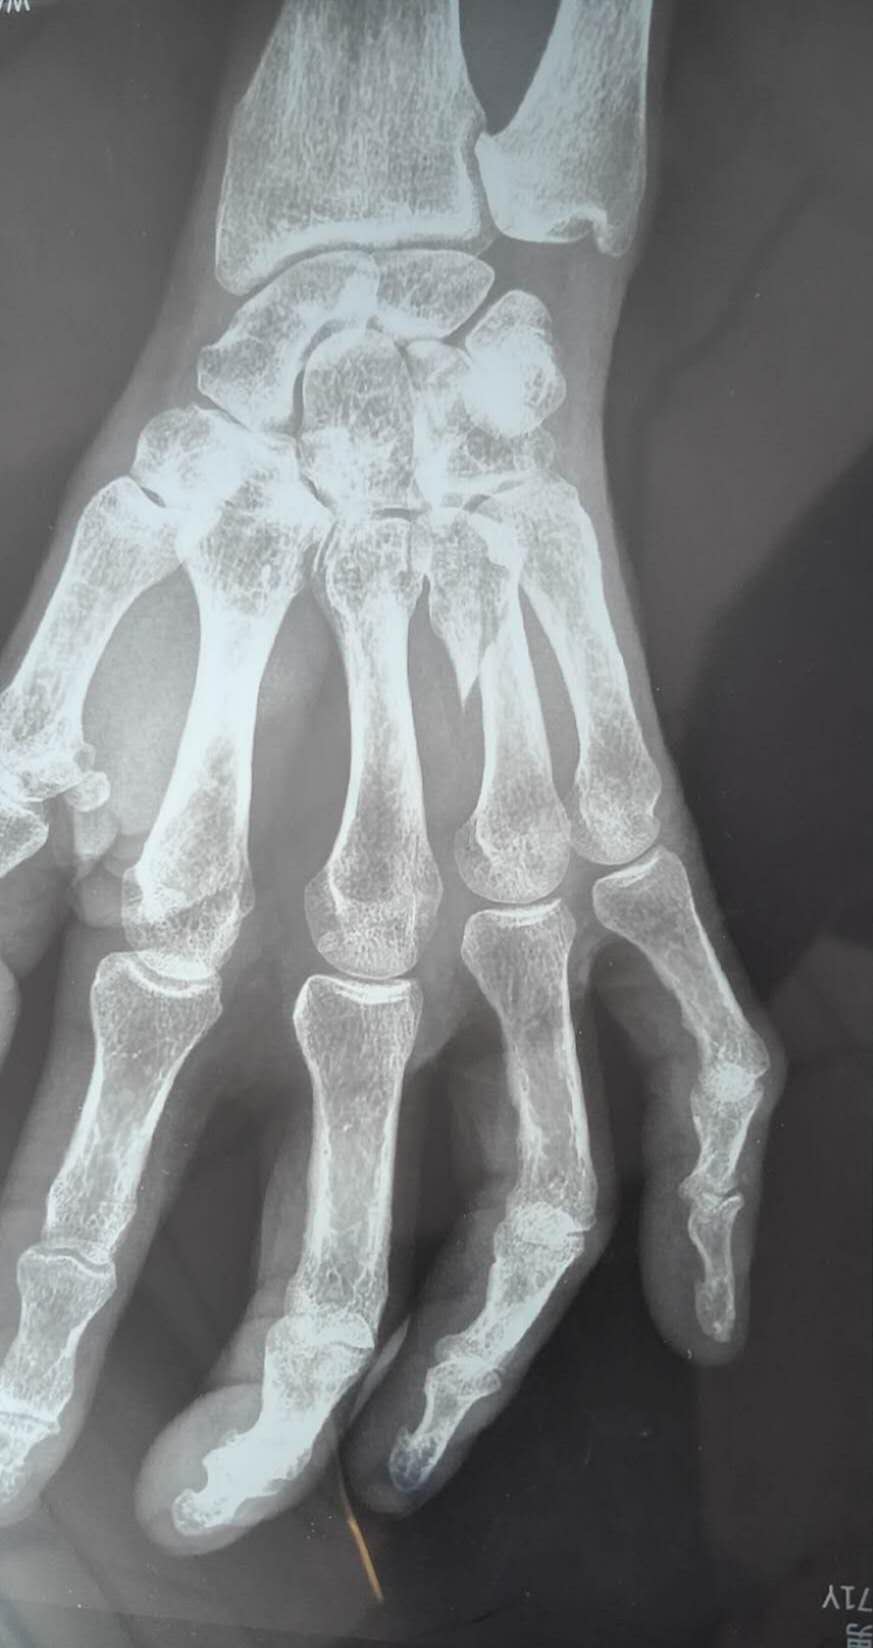

三、骨折:骨骼发出的「求救信号」

骨折部位CT影像图

图示说明:CT截面图展示骨折断端移位情况(如掌骨骨折),标注骨折线与错位方向。

跌倒、车祸等外力冲击常导致骨折,典型症状为剧烈疼痛、肢体畸形、反常活动(非关节部位出现异常活动)。开放性骨折(骨头刺破皮肤)更需紧急止血,避免感染。